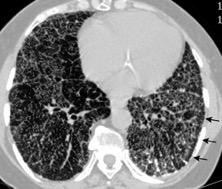

< 80% hallazgos pulmonares. Colección con calcificaciones. Micronódulos en intersticio subpleural y broncovascular con engrosamiento septal. Respuesta paradójica frecuente.

Vorsted MJ et al. Tuberculous pleural effusions: advances and controversias. J Thorac Dis 2015/ Wen P et al. Risk factors for tuberculous empyema in pleural tuberculosis patients. Sci Rep. 2019.